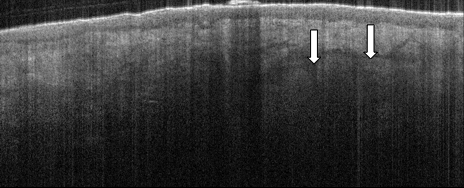

• Even if a descending hair cannot be seen, sebaceous glands are identifiable in the dermis by appearing more hyporeflective than their collagenous surroundings and the distinct change in texture